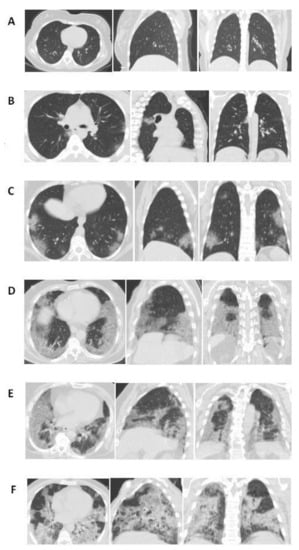

| Typical, n (%) | 316 (60.7) | 150 (48.5) | 166 (78.3) | <0.001 | |

| Bilateral, peripheral, and basal GGO with or without consolidation, n (%) | 301 (57.8) | 139 (45) | 162 (76.4) | <0.001 | |

| Bilateral, peripheral, and basalconsolidation, n (%) | 58 (11.1) | 27 (8.7) | 31 (14.6) | 0.036 | |

| Multifocal rounded GGO with or without consolidation, n (%) | 25 (4.8) | 21 (6.8) | 4 (1.9) | 0.01 | |

| Peribronchial enlargement, n (%) | 42 (8.1) | 20 (6.5) | 22 (10.4) | 0.108 | |

| Reversed halo sign, n (%) | 10 (1.9) | 4 (1.3) | 6 (2.8) | 0.209 | |

| Crazy paving pattern, n (%) | 10 (1.9) | 0 (0) | 10 (4.7) | <0.001 | |

| Indeterminate, n (%) | 61 (11.7) | 43 (13.9) | 18 (8.5) | 0.058 | |

| Unilateral GGO with or without consolidation, n (%) | 40 (7.7) | 34 (11) | 6 (2.8) | 0.001 | |

| Perihilar GGO with or without consolidation, n (%) | 4 (0.8) | 0 (0) | 4 (1.9) | 0.015 | |

| Diffuse GGO, n (%) | 5 (1) | 5 (1.6) | 0 (0) | 0.063 | |

| Few and small non-peripheric GGO, n (%) | 3 (0.6) | 3 (1) | 0 (0) | 0.15 | |

| Atypical, n (%) | 34 (6.5) | 10 (3.2) | 24 (11.3) | <0.001 | |

| Lobar pneumonia, n (%) | 4 (0.8) | 2 (0.6) | 2 (0.9) | 0.704 | |

| Effusion, n (%) | 16 (3.1) | 0 (0) | 16 (7.5) | <0.001 | |

| Interlobular septal thickening, n (%) | 6 (1.2) | 2 (0.6) | 4 (1.9) | 0.193 | |

| Pulmonary fibrosis, n (%) | 6 (1.2) | 2 (0.6) | 4 (1.9) | 0.193 | |

| Lymphadenopathy, n (%) | 2 (0.4) | 2 (0.6) | 0 (0) | 0.241 | |